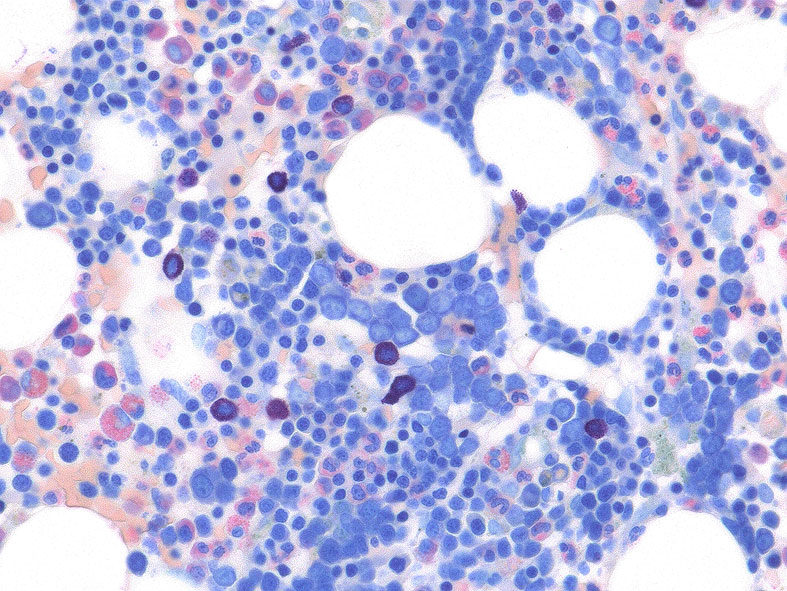

RARS(refractory anemia with ring sideroblasts:2016WHO分類ではMDS-RS)症例に見られたring sideroblastsです。(ベルリン青染色, x600)

Perlenkette (真珠の首飾り, ドイツ語)と呼ばれる青く染まった鉄顆粒が赤芽球の核周囲を取り巻くように認められます。

この青い顆粒はミトコンドリア内に貯留したフェリチン鉄ferritin ironです。

フェリチン鉄に満たされたミトコンドリアは丸い形が特徴です。seideroblastの青い顆粒も丸いことが特徴です。

定義では, 5個以上の鉄顆粒が, 赤芽球の核周囲1/3以上を囲むものとされている。

骨髄塗抹標本と組織(clot section)の鉄染色(クリックで大きな画像がみられます) ring sideroblastは鉄顆粒が核周囲にまとわりつくように見える赤芽球として認められる。Hb合成の乏しい幼若な大型赤芽球では認められる鉄顆粒は少ない。